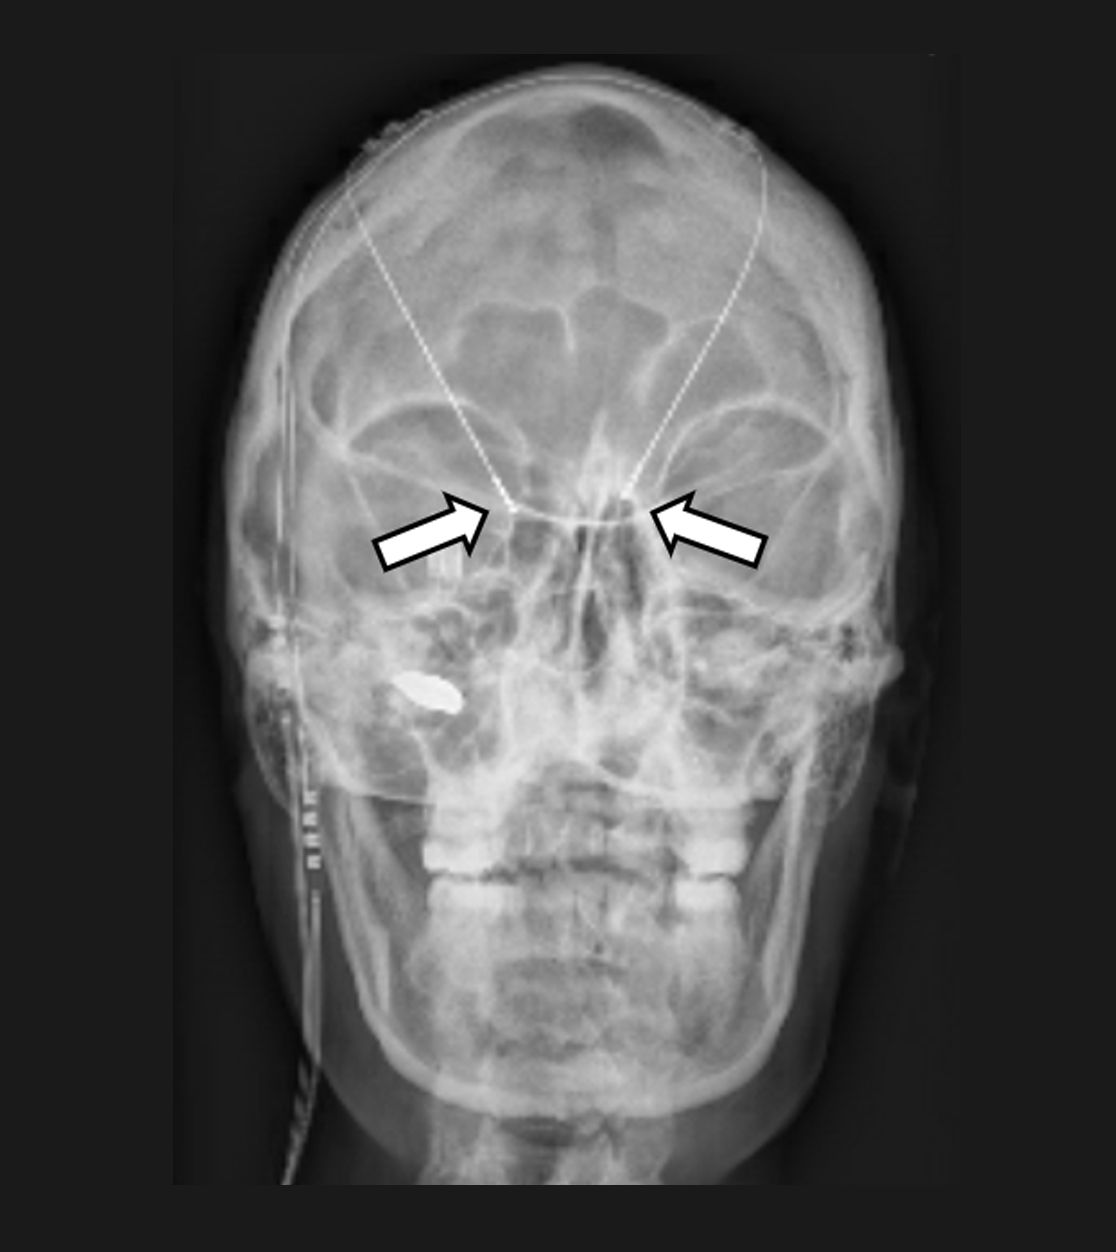

Die Tiefe Hirnstimulation, welche meist für Patienten mit Bewegungsstörungen wie Parkinson oder einer Dystonie eingesetzt wird, kann auch bei Patienten mit chronischen Gesichtsschmerzen oder einem sog. zentralen Schmerz zur Anwendung kommen. Es werden Elektroden gezielt mittels sog. stereotaktischer und robotischer Verfahren in kleine Kerngebiete des Gehirns implantiert und – wie bei anderen neuromodulativen Verfahren – an einen Impulsgeber (vergleichbar mit einem Herzschrittmacher) angeschlossen. Durch die Abgabe angepasster elektrischer Impulse sollen dann die Schmerzen gelindert und somit die Lebensqualität der Patienten verbessert werden. Wie bei der Motorcortexstimulation muss die Möglichkeit einer Tiefenhirnstimulation zur Schmerztherapie stets individuell evaluiert werden.

In das Gehirn implantierte Elektroden zur Tiefen Hirnstimulation (Pfeile)